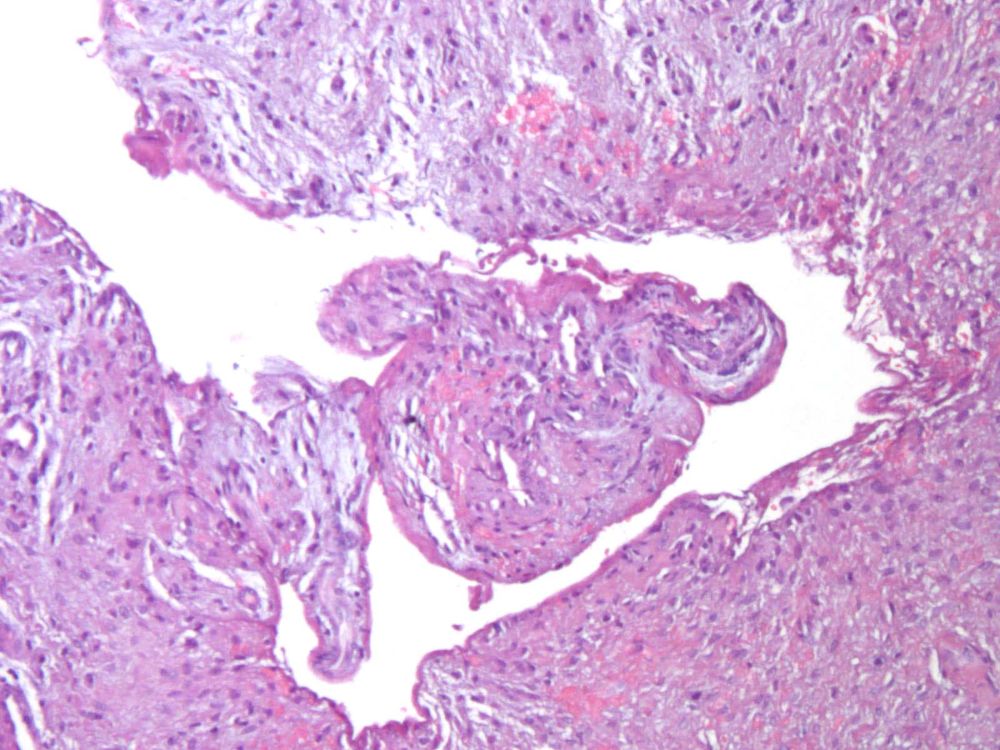

La muestra obtenida fue enviada en formaldehído al 10% para su análisis histopatológico, informando de los siguientes hallazgos:

- Descripción macroscópica: se remiten dos fragmentos, membranáceos, irregulares, parduzcos con zonas negruzcas, que miden en conjunto 1×1,2×0,5cm. se secciona el mayor y se incluyen en su totalidad.

- Descripción microscópica evidencia una lesión quística con una pared conectiva fibrocelular gruesa definida con estructuras vasculares dispersas y focos de inflamación crónica linfoplasmocitaria, hemorragia y depósitos hemosiderina. También se observan focos de inflamación mixta con numerosos macrófagos espumosos. En uno de los fragmentos se reconoce un recubrimiento epitelial poliestratificado no queratinizado fino delgado, focalmente desprendido. Periféricamente se observa una cáscara de tejido óseo vital trabecular (Figuras 13 y 14). El diagnóstico definitivo fue de quiste dentígero con inflamación crónica.